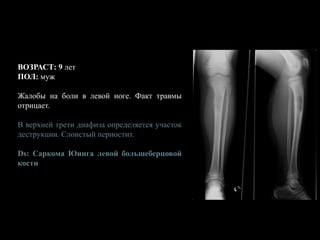

ВОЗРАСТ: 9 лет

ПОЛ: муж

Жалобы на боли в левой ноге. Факт травмы

отрицает.

В верхней трети диафиза определяется участок

деструкции. Слоистый периостит.

Ds: Саркома Юинга левой большеберцовой

кости